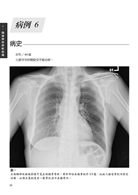

病例6 內固定骨釘異位(Malposition of internal fixation pin) 26